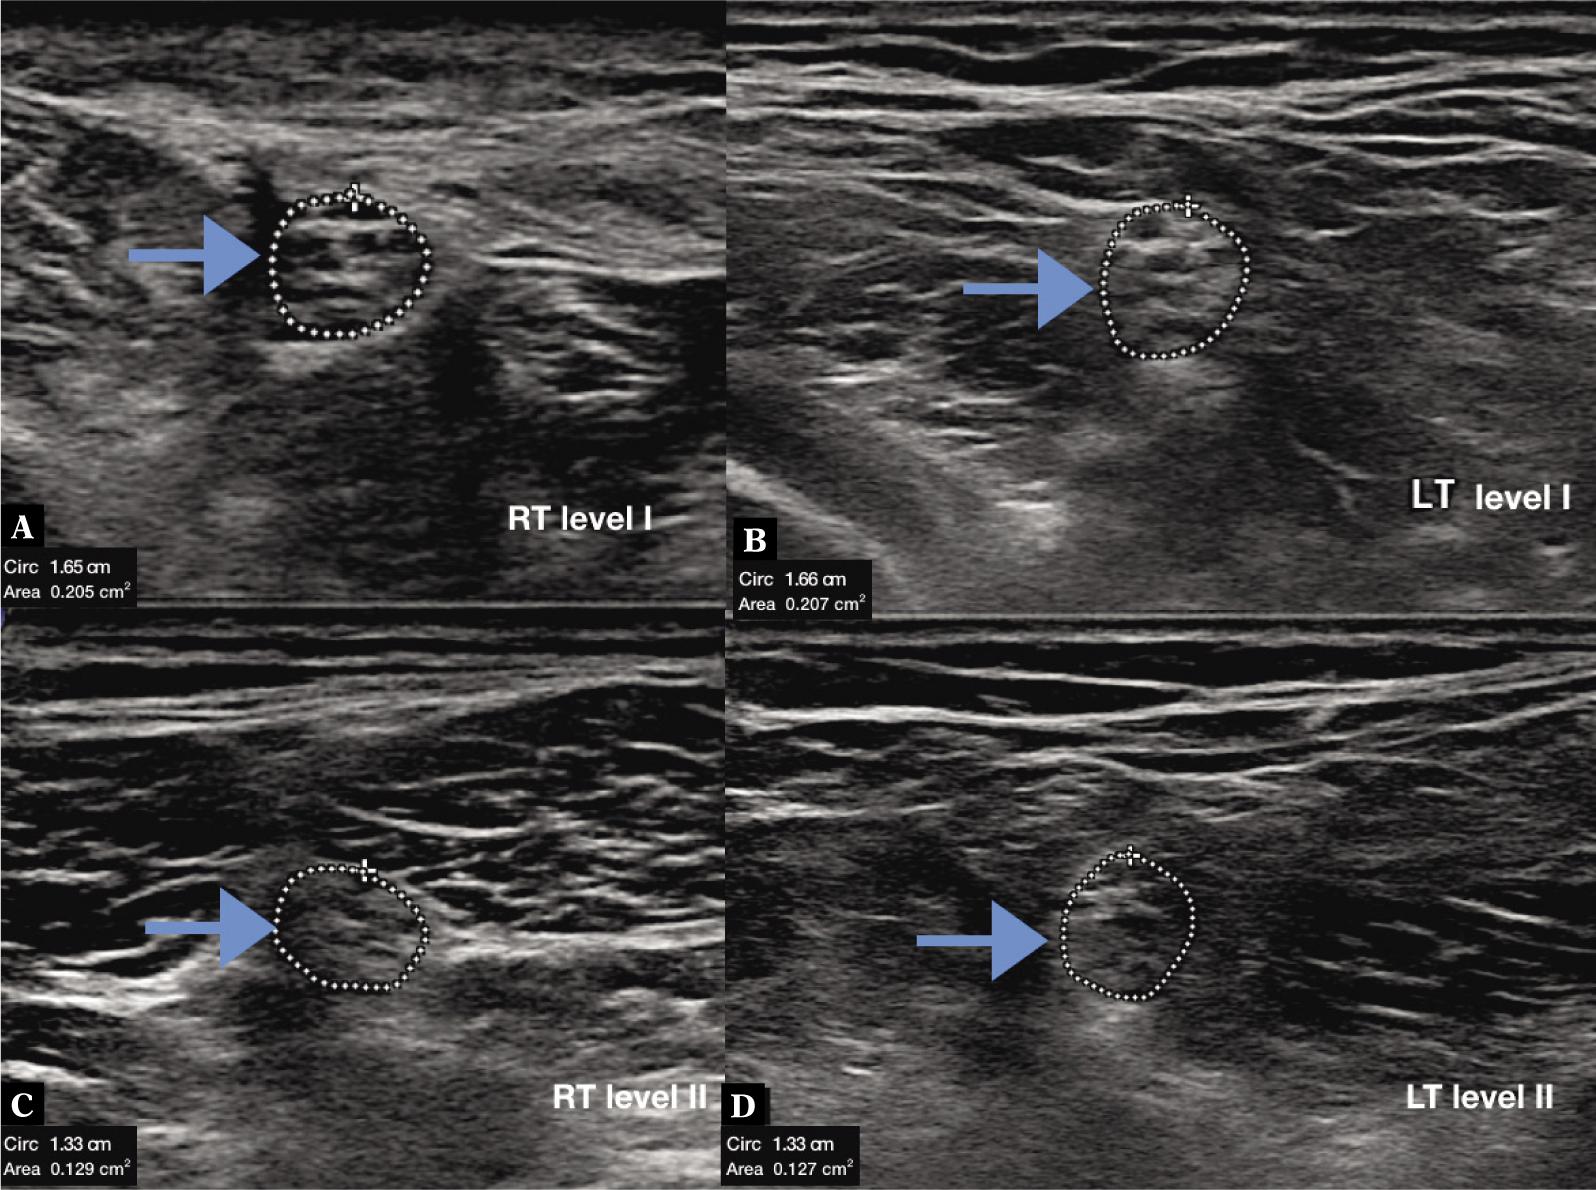

Fig. 4.

High resolution ultrasonography of normal tibial nerve at level I (A, B) and II (C, D) in bilateral lower limb in 61 years old male weighing 79 kg, having height of 177 cm and body mass index of 25.3. Cross sectional area was 0.205 cm2 and 0.207 cm2 at level I and 0.129 cm2 and 0.127 cm2 at level II in right and left lower limb respectively. (RT – right, LT – left, arrow – tibial nerve)